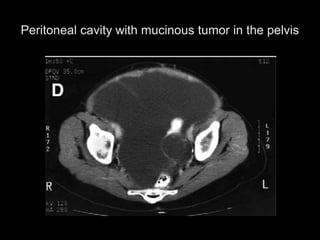

Pseudomyxoma peritonei (PMP) is a rare condition characterized by gelatinous ascites resulting from the rupture of appendiceal mucinous tumors, leading to significant abdominal complications. The incidence is approximately 2 cases per million per year, with a predominance in females, and diagnosis often relies on imaging techniques like ultrasound and CT scans. Effective treatment involves cytoreductive surgery combined with hyperthermic intraperitoneal chemotherapy (HIPEC) to manage disease progression and improve outcomes.